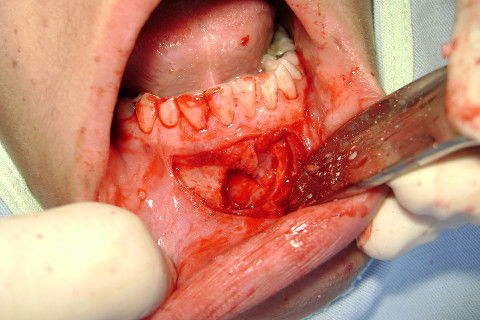

Incisão completa e inicio do descolamento com Molt 9.

Antes de começar a ostectomia com broca.

Ostectomia com broca esférica PM número 6. Bastante irrigação e cuidado.

Ostectomia completa com exposição da coroa, suficiente para execução da odontossecção. Com uma alavanca Seldin Reta o elemento foi levemente "sondado" para verificar o grau de mobilidade.